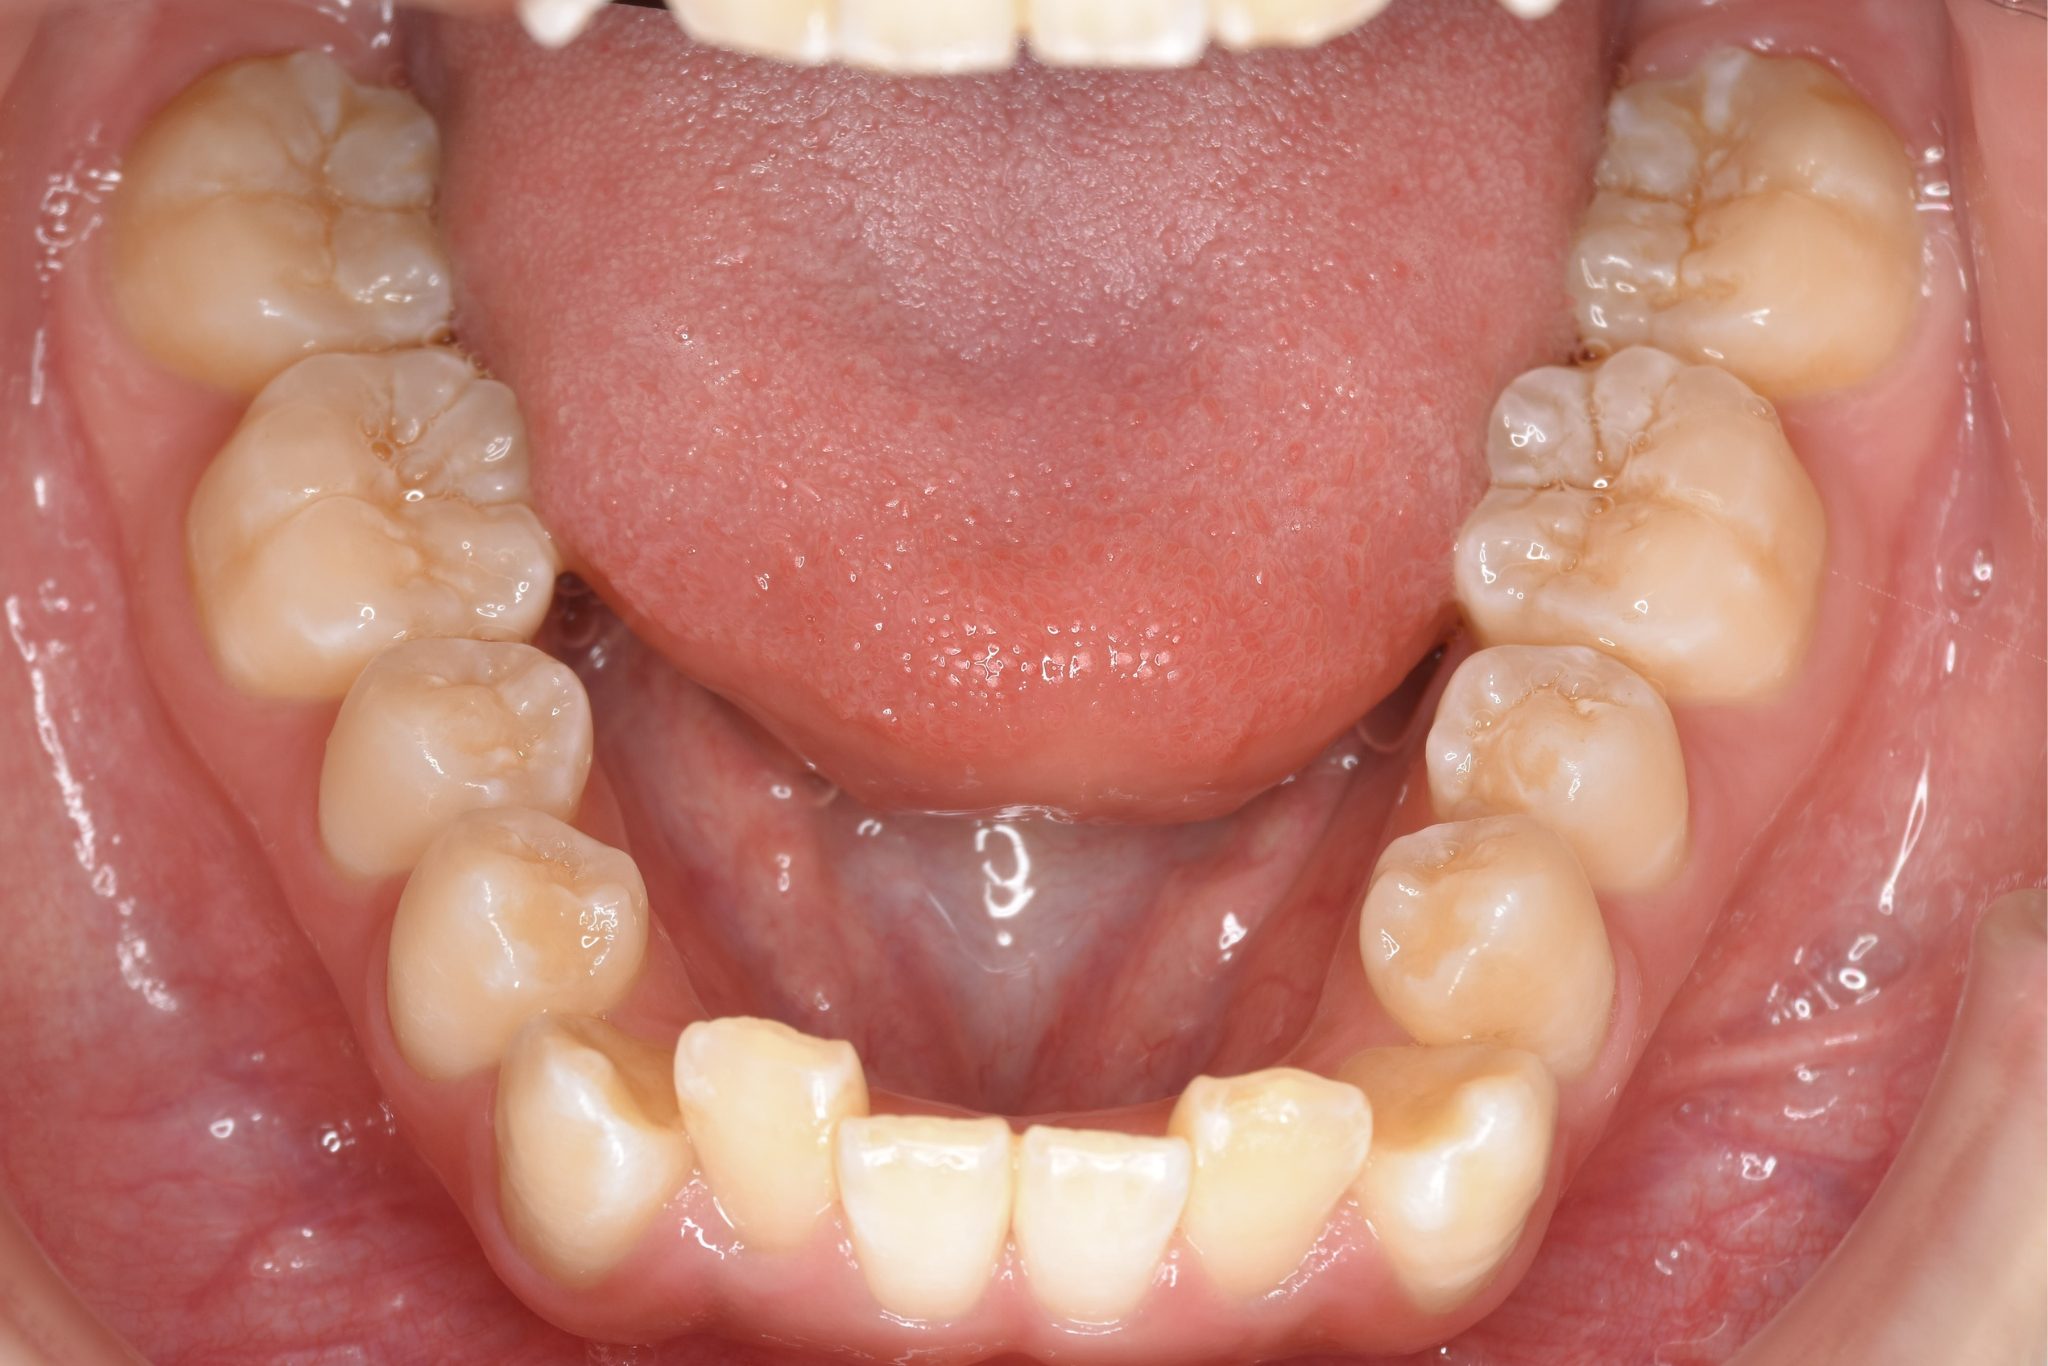

ビフォー

全顎ワイヤー矯正 症例_815

アフター

主訴 前歯の出っ歯|八重歯|下の歯のデコボコ|検診で噛み合わせが悪いと指摘されたこと

施術内容 成人矯正1期治療

治癒期間 1年4か月間

費用 954,800円(税込)